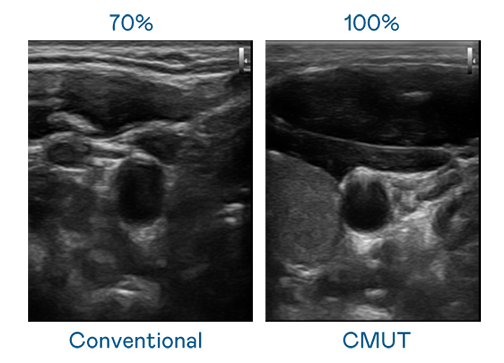

CMUT technology utilizes capacitive MEMS components to generate ultrasound signals. Compared to traditional ceramic piezoelectric technology, the 30% increased bandwidth of CMUT allows for wider ultrasound signals and greatly improved image resolution. This is a crucial technology for achieving medical ultrasounds with high-quality images and promoting the development of precision medicine.

Ultra-wide bandwidth offers high-quality images

The image quality of medical ultrasound depends on the signal bandwidth the ultrasound transducer can emit. AUO's CMUT offers high-resolution ultrasound signals with ultra-wide bandwidth and high sensitivity for more delicate image texture and details to help ultrasound medical examiners reduce time on interpreting and diagnosing based on precise medical images.